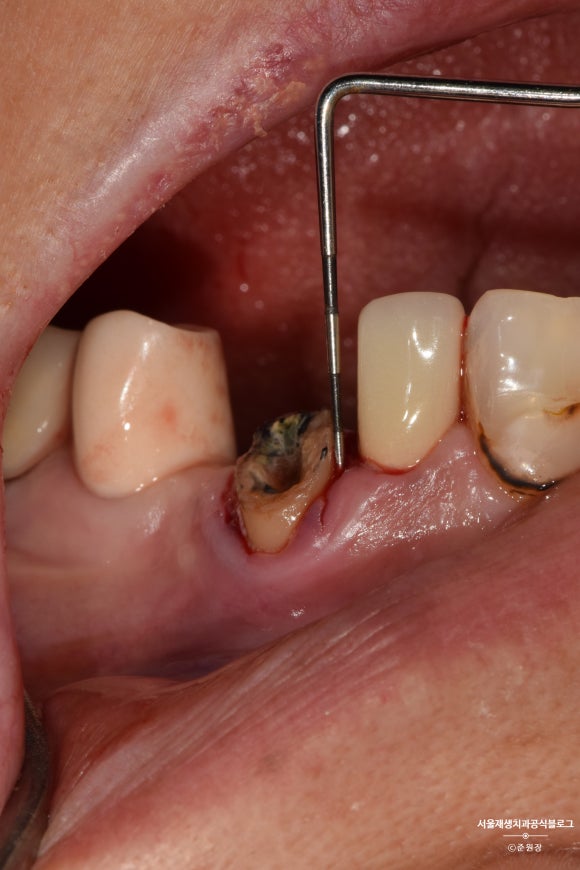

충분한 높이가 확보되었는지 확인하기 위한 치주탐침검사입니다. 눈금이 있어서 '자'처럼 쓸 수 있는 유용한 도구입니다^^

크라운을 씌우기 위해서는 최소 2~3mm의 높이가 필요합니다.